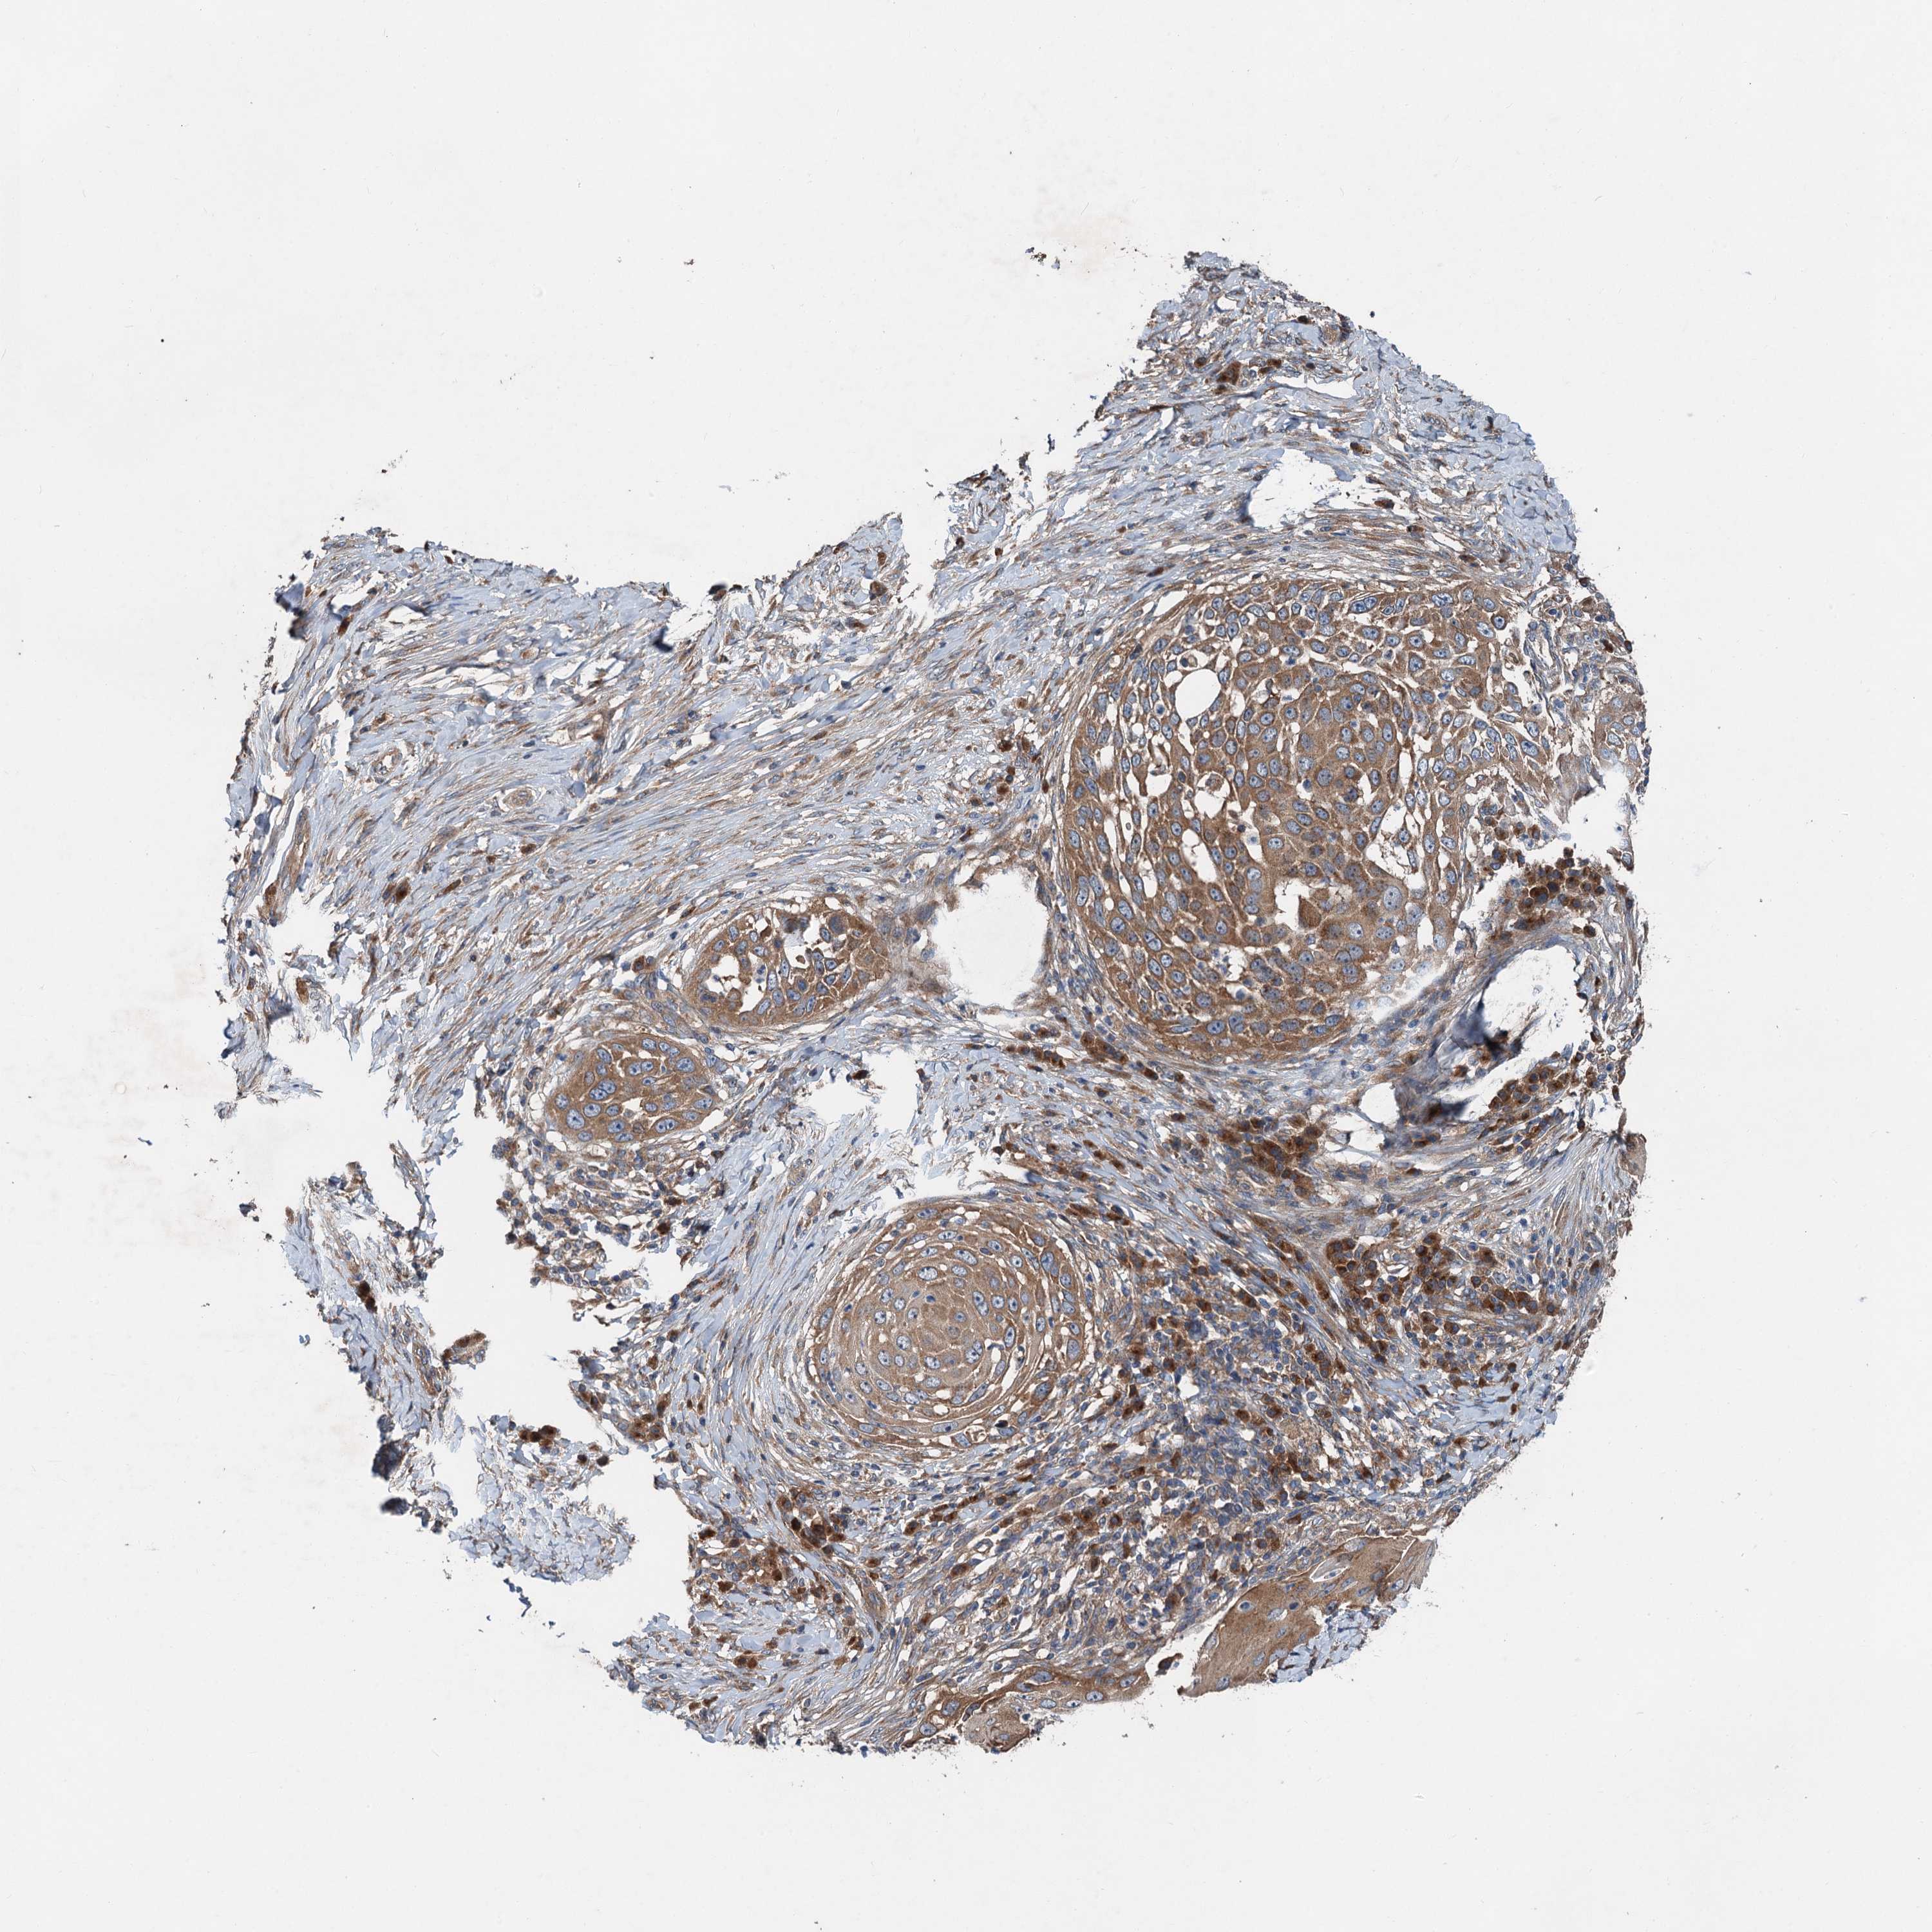

SKIN CANCER - Protein expressioni

A mouse-over function shows sample information and annotation data. Click on an image to view it in a full screen mode. Samples can be filtered based on level of antibody staining by selecting one or several of the following categories: high, medium, low and not detected. The assay and annotation is described here.

Antibody stainingi

Antibody staining in the annotated cell types in the current human tissue is reported as not detected, low, medium, or high, based on conventional immunohistochemistry profiling in selected tissues. This score is based on the combination of the staining intensity and fraction of stained cells.

Each image is clickable and will lead to virtual microscopy that enables deeper exploration of all samples and also displays staining intensity scores, fraction scores and subcellular localization as well as patient and tissue information for each sample.

Antibody HPA040353

Staining

High

Medium

Low

Not detected

Intensity

Strong

Moderate

Weak

Negative

Quantity

>75%

75%-25%

<25%

None

Location

Nuclear

Cytoplasmic/membranous

Cytoplasmic/membranous,nuclear

Basal cell carcinoma

Squamous cell carcinoma, NOS

Squamous cell carcinoma, metastatic, NOS